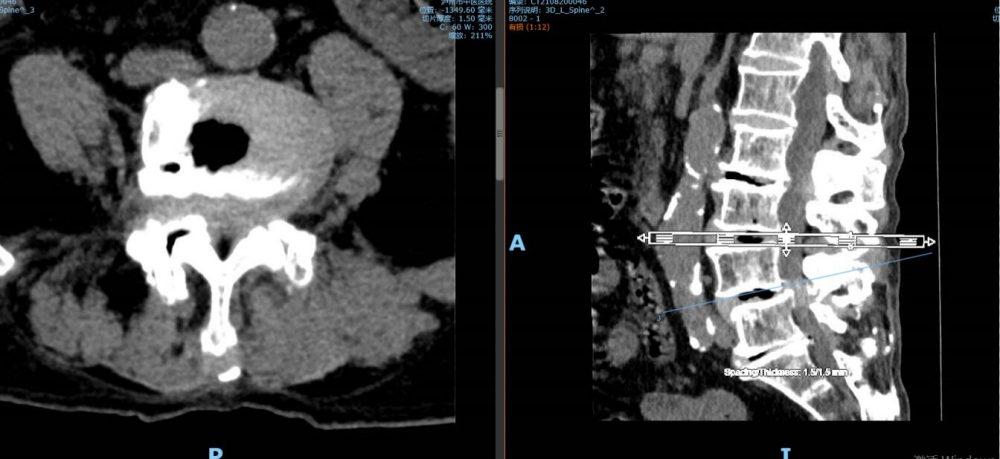

“我‘考試’去了,你們不要擔(dān)心”。8月27日上午8點(diǎn),92歲高齡的李謹(jǐn)行老人被推進(jìn)了瀘州市中醫(yī)醫(yī)院的手術(shù)室,進(jìn)手術(shù)室前,老人樂觀地寬慰著兒女們。此番,醫(yī)生將為老人進(jìn)行骨科手術(shù),若手術(shù)成功,老人將結(jié)束幾乎癱瘓?jiān)诖驳娜兆樱焕先送瑫r(shí)還患有腰椎管狹窄癥等17種疾病,這樣的情形下,無論是對(duì)老人的身體還是醫(yī)生而...